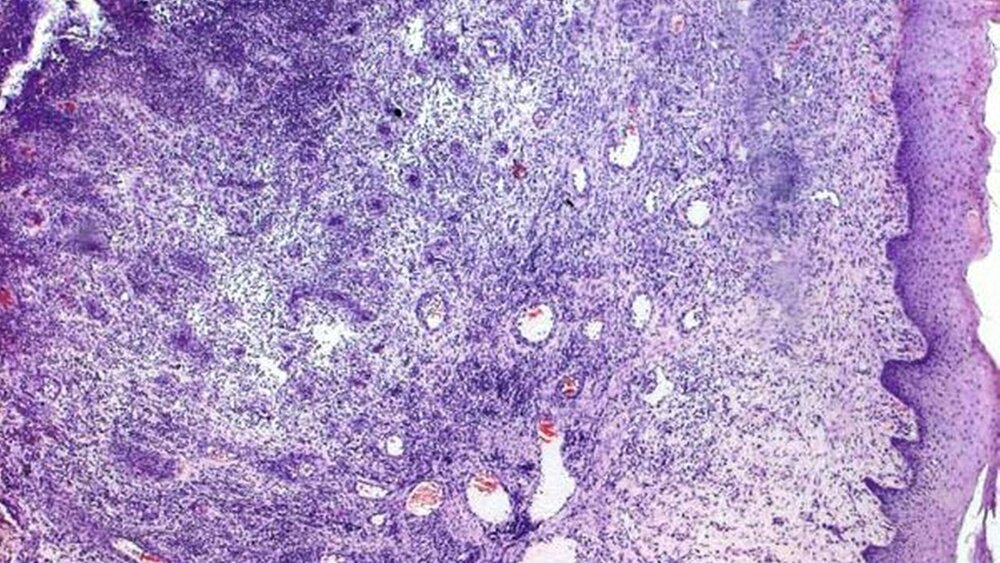

Das für die Epulis granulomatosa charakteristische histologische Bild mit läppchenförmig gegliedertem Gewebe, zahlreichen Kapillaren und einer Infiltration mit neutrophilen Granulozyten bestätigte im aktuellen klinischen Fall die Arbeitsdiagnose.

Weitere drei Wochen später stellte sich die extraorale Schwellung unverändert dar. Der Patient war jetzt beschwerdefrei. In regio 24 – 27 hatte sich eine etwa 3 x 2 x 1,5 cm3 große, rötliche, nicht druckdolente, weiche Geschwulst gebildet (Abbildung 2). Unter der Arbeitsdiagnose Epulis granulomatosa wurde die Läsion unter Mitnahme des Periostes mit dem Skalpell exzidiert. Der darunterliegende Knochen ließ keine Veränderung erkennen, so dass auf eine modellierende Osteotomie verzichtet werden konnte. Allerdings konnte eine Verbindung der Geschwulst mit dem periimplantären Gewebe des Implantates in regio 27 identifiziert werden. Das Implantat selbst wies im Vergleich zu den Implantaten 24 und 25 einen dumpfen Klopfschall sowie eine geringgradige Mobilität auf. Die weitere Exploration detektierte eine bindegewebige Einheilung des Implantates 27 und erforderte die sofortige Explantation. Das Implantatbett wurde vollständig kürettiert (Abbildung 3). Die histopathologische Begutachtung durch Priv.-Doz. Dr. Andreas Gaumann, Institut für Pathologie der Universität Regensburg, bestätigte die Arbeitsdiagnose einer Epulis granulomatosa (Abbildung 4). Die Schwellung der Wange war nach vier Tagen nicht mehr vorhanden, ein Rezidiv der Epulis trat bis heute nicht auf. Nach dreimonatiger Konsolidierungsphase wurde in regio 27 ein neues Implantat inseriert, welches inzwischen freigelegt und versorgt werden konnte.